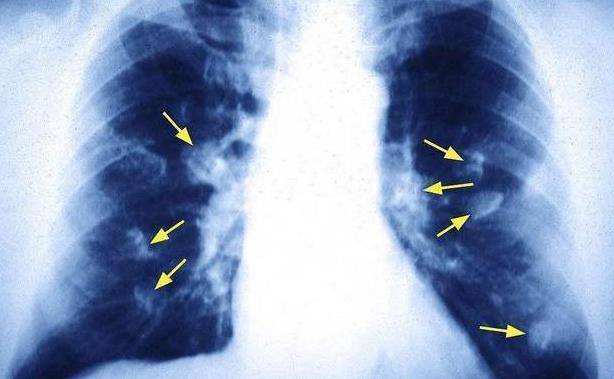

■肺部受损时,身体会出现求救信号,变化很明显,别当肺癌到来才后悔!

●日常生活中,久咳不愈时就需要警惕,一般引起咳嗽的原因有很多,比如喝水不小心呛到了、比如感冒了、呼吸道感染等等;通常持续时间并不是很长,甚至是在用药之后就能够缓解和改善。倘若你的身体没有其他问题,又或是用药之后,咳嗽问题也就没有缓解和改善,那么可能就是肺部在向你求救,肺部一旦受损,就会影响到呼吸道的正常运作,继而引起咳嗽不止的情况。

●胸部出现剧烈疼痛,肺部主要分布在我们胸腔的两侧,一旦肺部出现了问题,那么就会出现不同程度上的疼痛。如果你对此没有给予重视,当它发展到某些特定的程度时,这种疼痛感就会有所加剧,甚至还可能会转变成持续性的刺痛感或是钝痛感,隐患就更大了。

●日常生活中,常常会出现呼吸急促,又或呼吸时有哨音,甚至偶尔还会出现喘不过气,问题并不是很大。倘若你在进行比较轻度活动时,又或是没有进行活动时,总是感觉喘不上气,那么就需要警惕了。肺部一旦损伤,里面液体增加或是有异物阻挡,那么就会导致呼吸不畅。